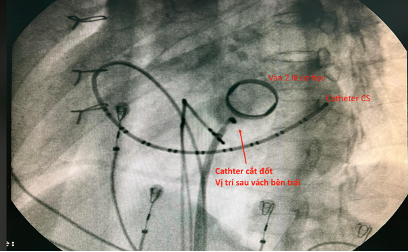

Thủ thuật cắt đốt điện sinh lý được tiến hành ngày hôm sau nhập viện. Trong phòng cath lab ghi nhận bệnh nhân có đường dẫn truyền phụ thành sau vách. Chọc vách liên nhĩ thăm dò vùng nội mạch sau vách bên thất trái gần van 2 lá cơ học ghi nhận điện thế nhĩ thất hoà vào chưa hoàn toàn và vị trí này vì có van 2 lá cơ học nên không tiếp cận mặt thất được.

Hình: chọc vách liên nhĩ và thăm dò thành sau vòng van 2 lá cơ học bên trái nghiêng phải – trái.